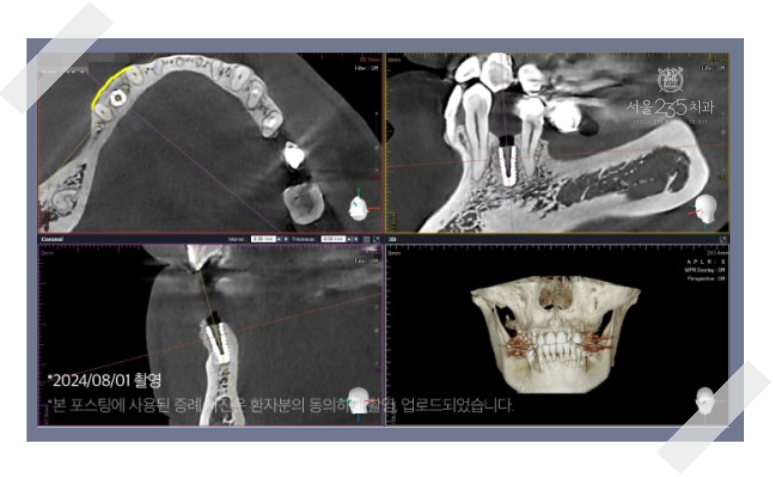

CT촬영을 해보면 임플란트를 심기에는 뼈의 폭이

매우 얇거나 높이가 현저히 낮은 상태인 것을 확인할 수 있습니다.